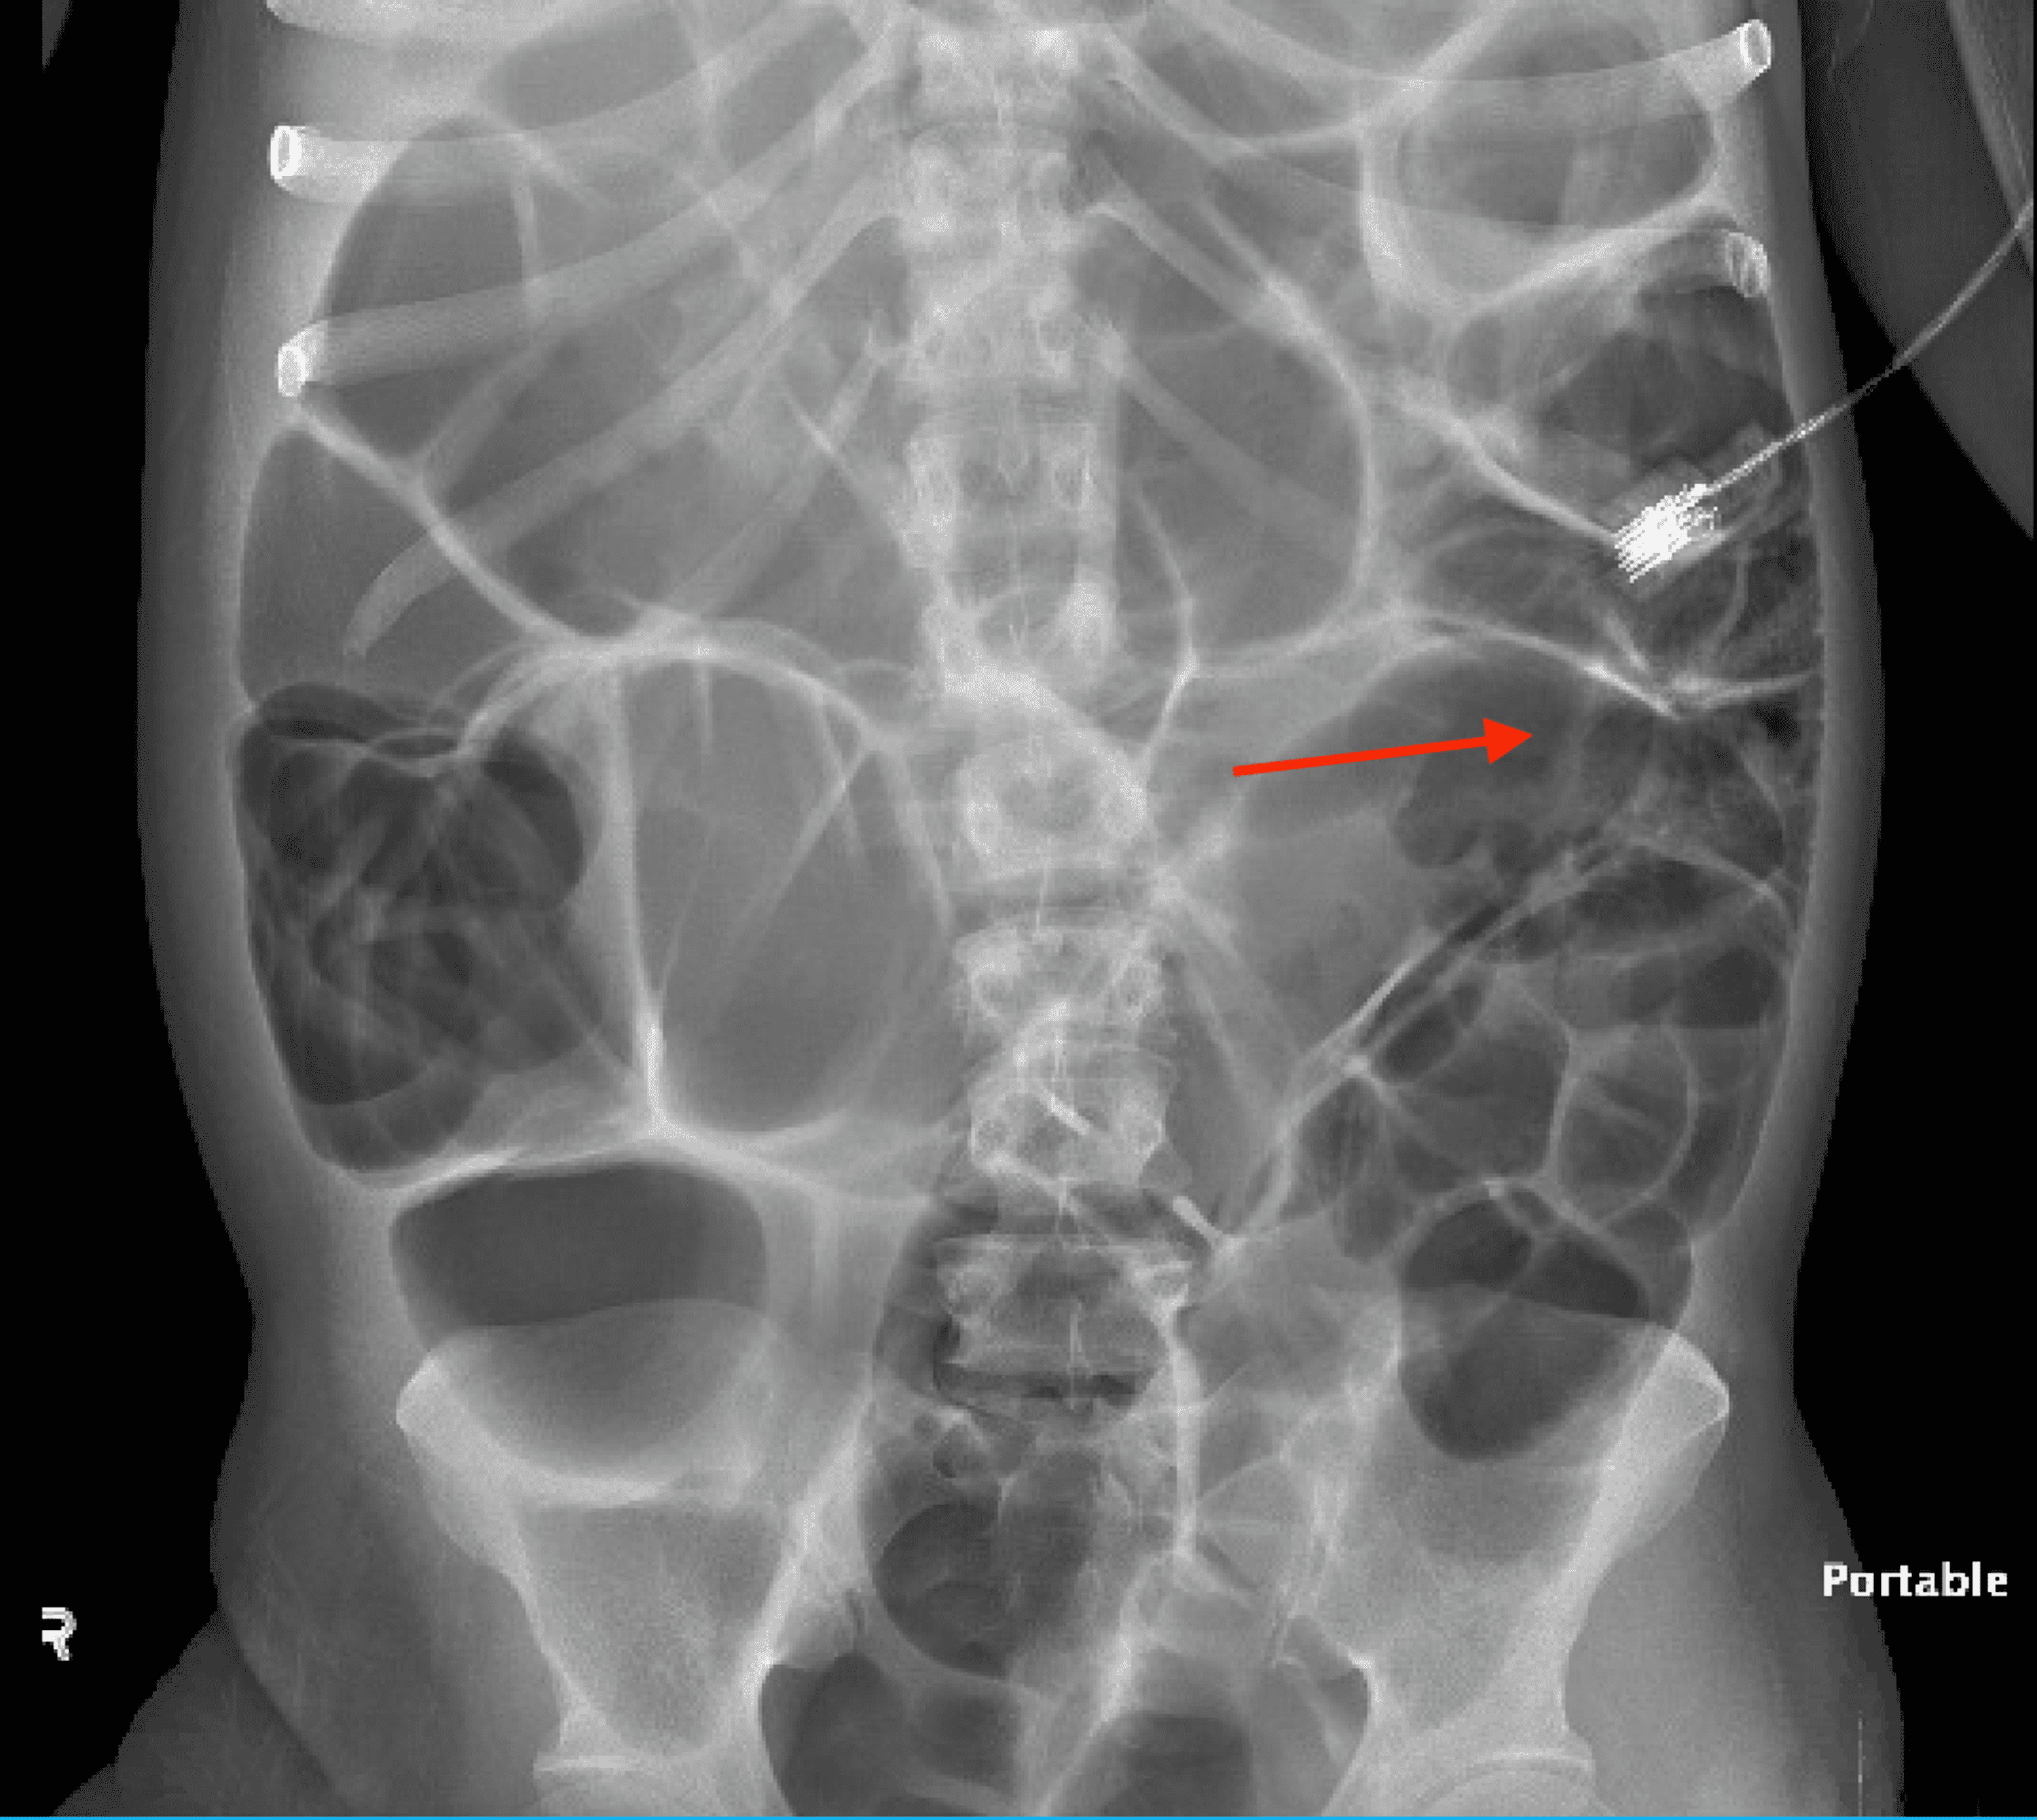

From wikidoc.org

Ischemic colitis abdominal x ray wikidoc Ischemic Colitis Flying colonic ischaemia is the most common type and has the most favourable prognosis. risk factors for ischemic colitis include: the diagnosis of ci is usually established in the presence of symptoms including sudden cramping, mild, abdominal pain; A few hours after arrival she developed vomiting, diarrhoea,. An urgent desire to defecate;. a 43 year old woman. Ischemic Colitis Flying.